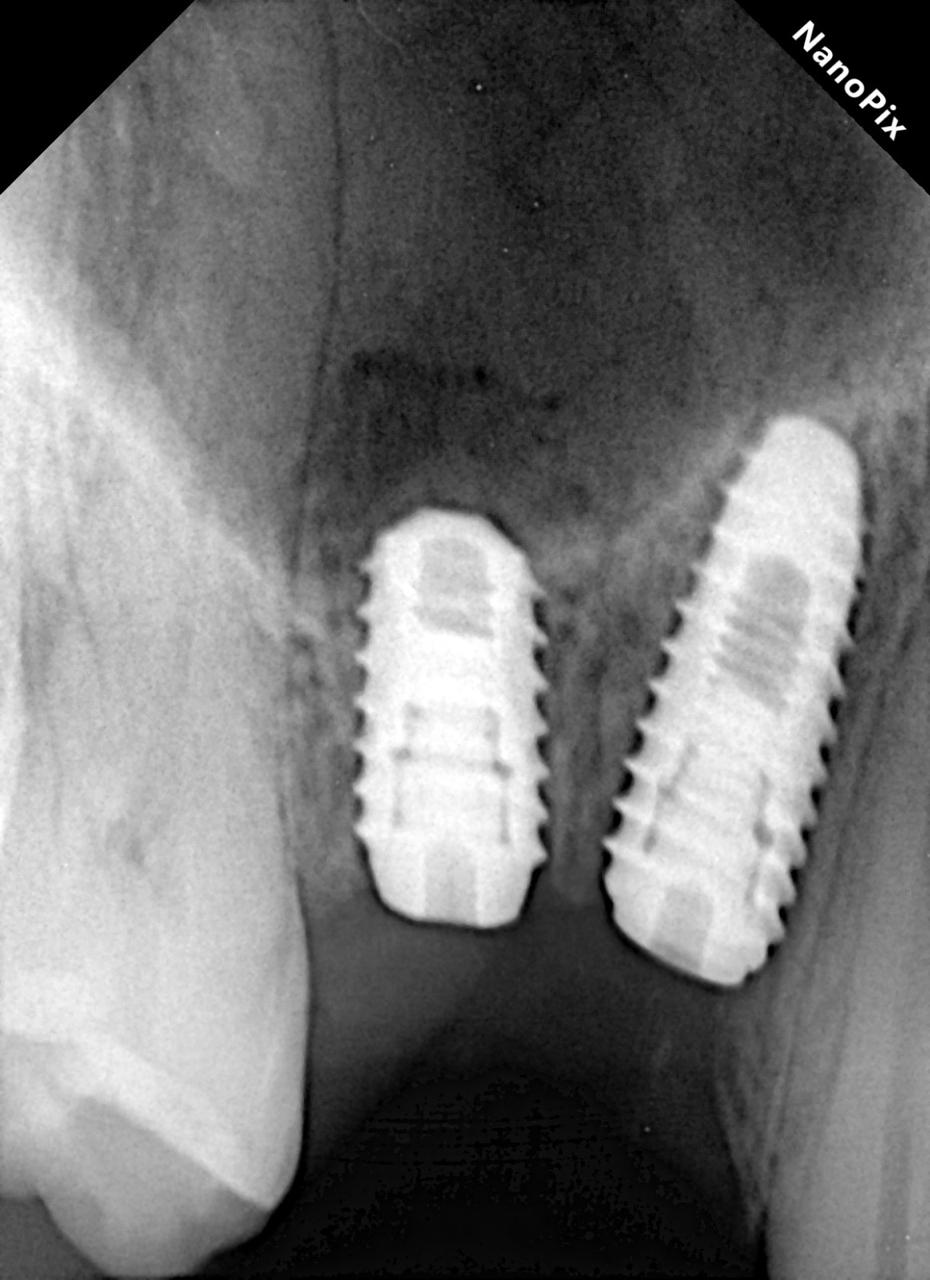

There are 2 types of x rays, intraoral and extra oral. Intraoral X rays are taken inside the mouth and an extra oral x-ray is taken outside the mouth. Intraoral X rays are more common and help your dentist in:

- Checking bone and jaw health

- Judging overall oral health